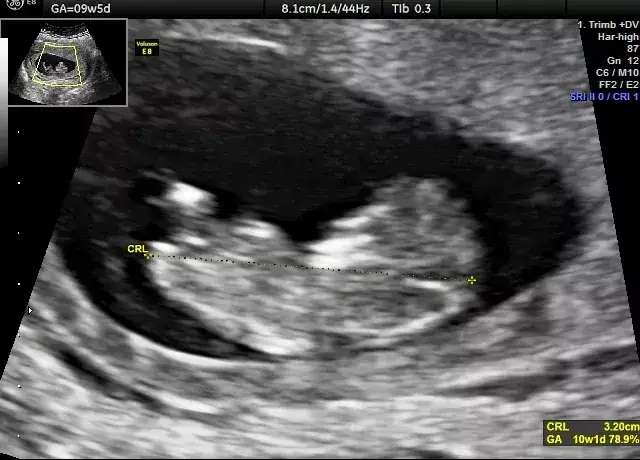

Kiedy pierwsze USG w ciąży? Poznaj optymalne terminy, cel badań i co oznaczają wyniki. Sprawdź poradnik PTGiP i rozwiej obawy!